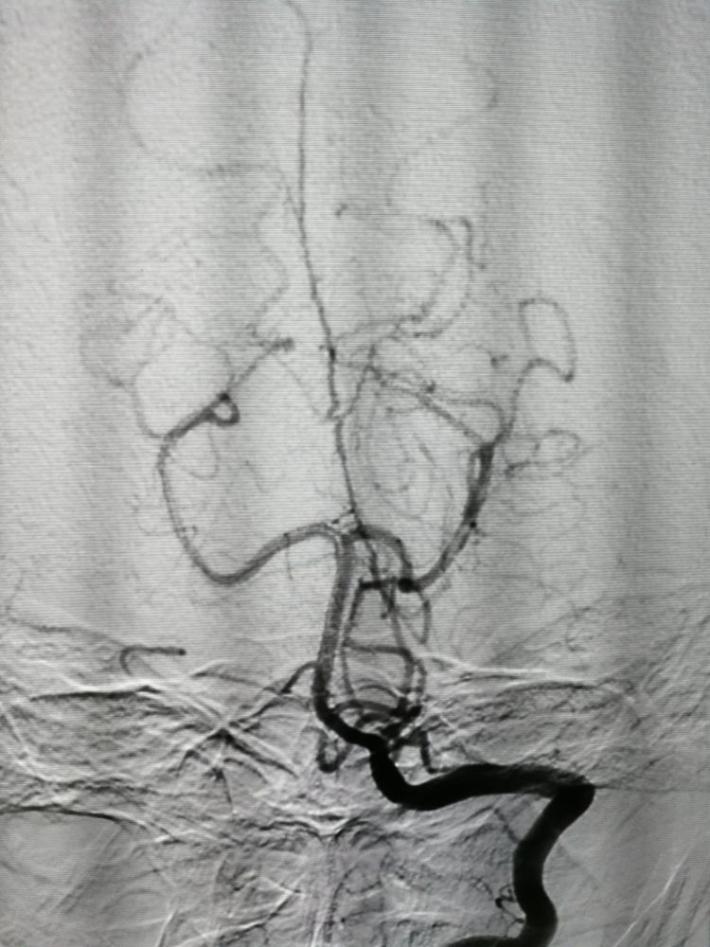

拟行介入栓塞术,术前(发病一周)再造影,前交通动脉瘤“消失了”!

以原造影3D为依据,选择一角度再造影,见动脉瘤“若隐若现”,但路图上动脉瘤仍不显影,仔细观察血管,见同侧A1、回返动脉较前一日痉挛,分析系此因素加上动脉瘤小且窄颈的原因导致造影剂进入动脉瘤内太少,以致动脉瘤显影不良。考虑瘤体很小,路图上又不显示,盲目栓塞风险很大,决定终止手术,改行开颅夹闭。